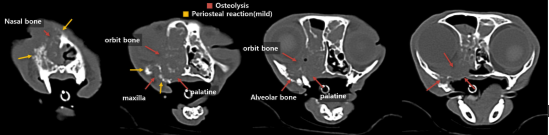

정확한 환자 상태 평가 및 확정진단을 위하여 전신 CT 촬영 및 조직 검사를 계획하였습니다.

고양이 구강 SCC 내원 당시 CT 검사 1 / 출처: 에스동물암센터

📌CT 검사 결과

이번 영상 검사에서 확인된 병변은 위턱뼈(상악)에서 시작된 병변일 가능성이 가장 높습니다. 뼈가 녹아내리는 모습(bone lysis)과 뼈 표면이 반응하는 소견(periosteal reaction)이 보여, 악성 종양일 가능성을 우선적으로 고려해야 합니다.

다만, 코(비강)에서 시작된 병변이 위턱뼈로 퍼진 것일 가능성도 완전히 배제할 수는 없습니다. 따라서 정확한 원인을 알기 위해서는 조직 검사가 필요합니다.